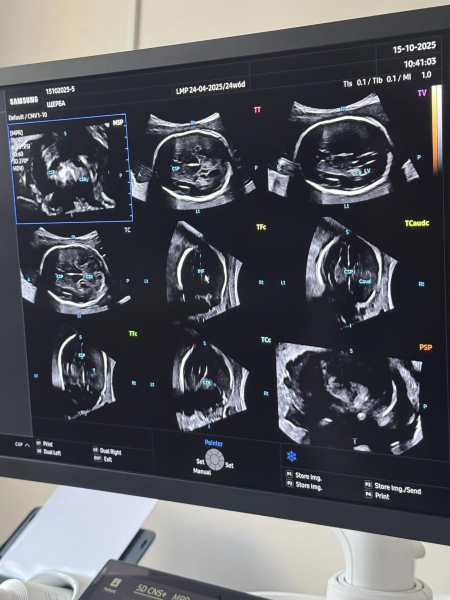

У Центрі планування сім’ї та репродуктивного здоров’я Вінницької обласної клінічної лікарні ім. М. І. Пирогова встановлено перший в Україні ультразвуковий апарат нового покоління — Samsung HERA Z20. Система поєднує штучний інтелект і 5D-візуалізацію для максимальної точності та деталізації.

"HERA Z20 автоматично розпізнає анатомічні структури, проводить точні вимірювання та формує об’ємні зображення в реальному часі. 5D Ultra Live, Crystal Architecture™ та AI ScanAssist забезпечують неймовірну реалістичність — батьки можуть побачити обличчя й рухи своєї дитини ще до народження. Для лікарів це — можливість виявляти найменші відхилення розвитку на ранніх етапах і приймати рішення, що рятують життя", – йдеться у повідомленні.

Апарат відкриває новий стандарт пренатальної діагностики, спостереження за вагітністю та охорони репродуктивного здоров’я жінок.